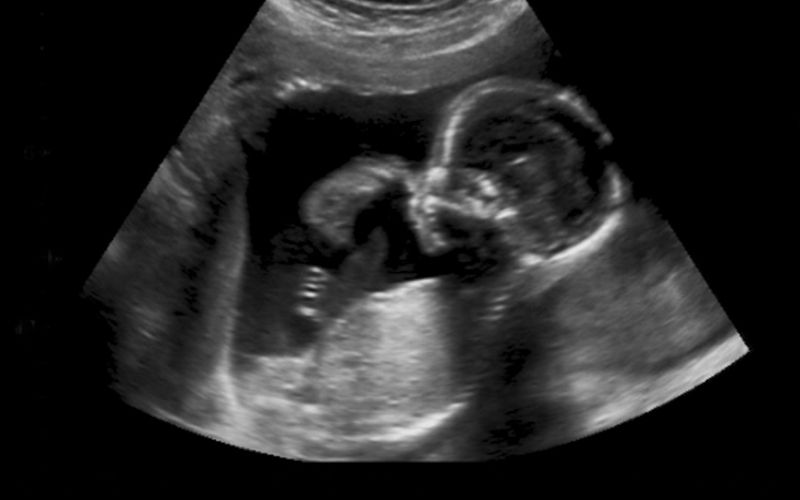

Siêu âm dị tật thai nhi là phương pháp sàng lọc những bất thường của thai nhi bằng sóng siêu âm có tần số cao. Những bất thường đó có thể là nhiễm sắc thể, hình thái các cơ quan, bộ phận của bào thai.

Bản chất của phương pháp này là sóng âm được truyền từ máy siêu âm đến tử cung người mẹ, thu nhận hình ảnh thai nhi trong bụng và hiển thị trên màn hình. Qua đó, chúng ta có thể quan sát cụ thể về hình dáng, vị trí và những cử động của thai.

Nhờ siêu âm, cha mẹ không những có thể theo dõi được quá trình phát triển của thai nhi mà còn phát hiện ra những dị tật của thai nhi với độ chính xác 80-90%. Từ đó có thể chủ động can thiệp, điều trị bằng các phương pháp phù hợp nhất.